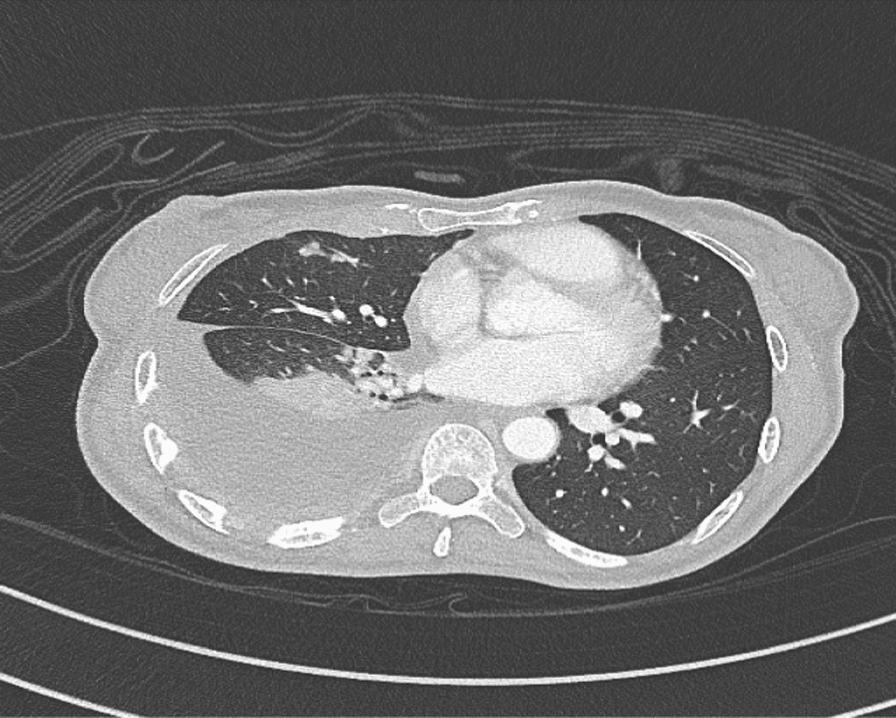

We are reporting a case of primary ovarian neuroendocrine neoplasm in association with an epithelial borderline tumor. She is a 50-year-old Filipino woman who presented with nonspecific symptoms. Initial imaging revealed a large mass with suspicion of widespread metastasis. However, further imaging and laparotomy revealed early-stage neuroendocrine neoplasm, a large borderline epithelial tumor, with no evidence of pulmonary metastasis, despite having pleural effusion. She was lost to follow-up, presented again after a year with evidence of residual disease/metastasis, and was treated with chemotherapy.

我们报告一例原发性卵巢神经内分泌肿瘤合并上皮性交界性肿瘤的病例。患者为一名50岁的菲律宾女性,出现非特异性症状。初始影像学检查发现一个大肿块,怀疑有广泛转移。然而,进一步的影像学检查和剖腹手术显示为早期神经内分泌肿瘤,一个大的交界性上皮性肿瘤,尽管有胸腔积液,但无肺转移证据。她失访了,一年后再次就诊,有残留疾病/转移的证据,并接受了化疗。